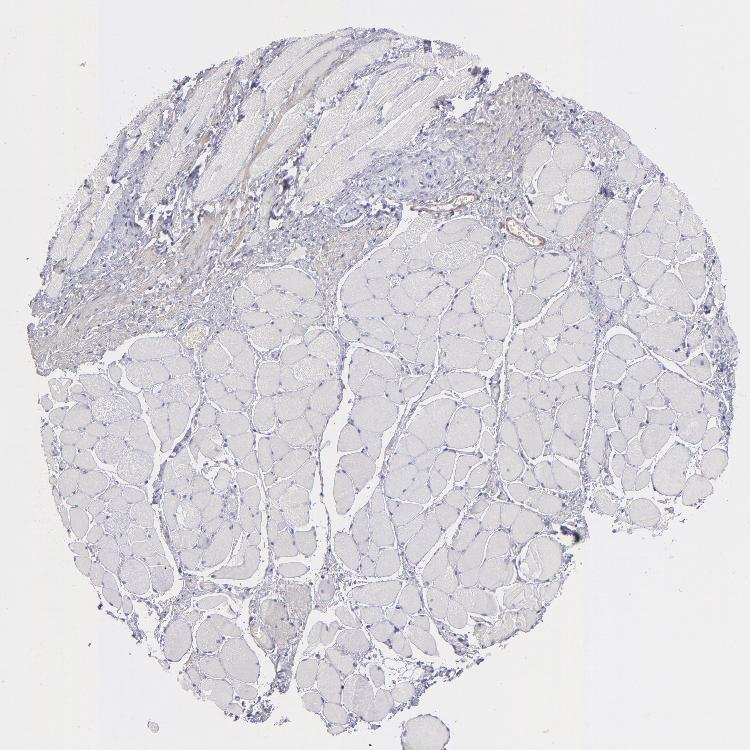

TISSUE PRIMARY DATA ESOPHAGUS Show tissue menu

Esophagus

ESOPHAGUS - Antibody stainingi

Antibody staining in the annotated cell types in the current human tissue is reported as not detected, low, medium, or high, based on conventional immunohistochemistry profiling in selected tissues. This score is based on the combination of the staining intensity and fraction of stained cells.

Each image is clickable and will lead to virtual microscopy that enables deeper exploration of all samples and also displays staining intensity scores, fraction scores and subcellular localization as well as patient and tissue information for each sample.

Antibody HPA014539Antibody HPA015310Antibody CAB002302

Squamous epithelial cells Not detectedNot detectedNot detected